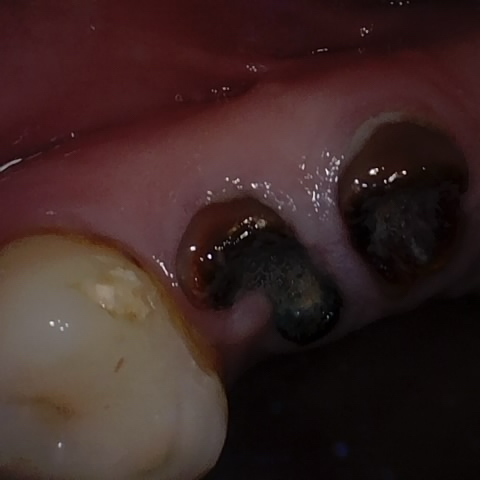

Annotated as "Good"